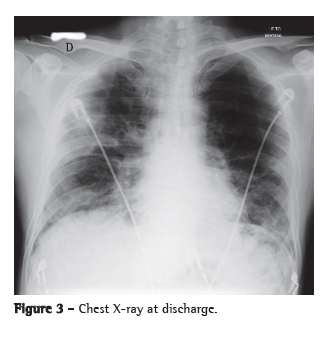

The patient was admitted to the ICU and treated with oseltamivir, ceftriaxone, azithromycin and a corticosteroid. He received ventilatory support with intermittent positive pressure breathing, which was maintained at 50% via a Venturi mask, at a resting SpO2 of 92%. The patient progressively improved and was discharged from the ICU ten days later, presenting an SpO2 of 94% on room air, together with radiological improvement (Figure 3). He developed no fever or hemodynamic instability during the hospital stay.

The most common radiological manifestations of influenza pneumonia consist of reticulonodular opacities, with or without superimposed areas of consolidation. Less commonly, patients with influenza pneumonia can present with focal areas of consolidation, typically in the lower lobes, without apparent reticular or reticulonodular opacities. The radiological abnormalities typically resolve in approximately three weeks. Consolidations can occur due to secondary bacterial pneumonia.(7,8)